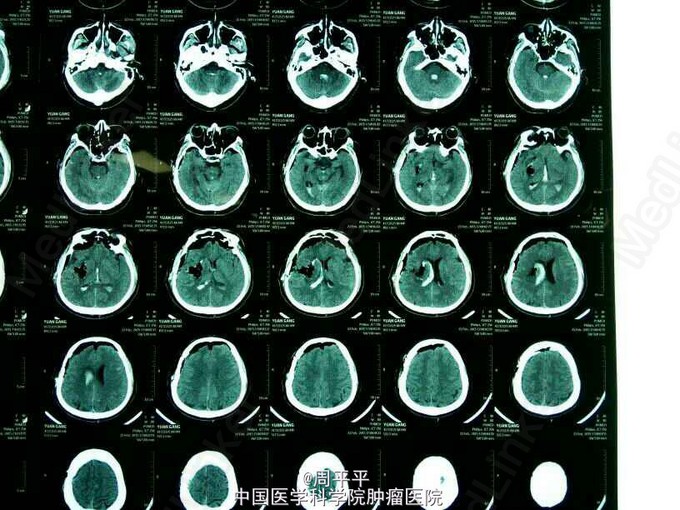

患者44岁男性,晨起发现左侧肢体无力,伴有言语不清,烦躁,入院后查CT(图1)考虑右侧基底节区出血,急诊行“开颅颅内血肿清除术”,术中取出的血凝块(图2),术后又复查CT(图3),脑实质出血已经基本上清除干净,右侧脑室、三四脑室仍有少量残留的出血。